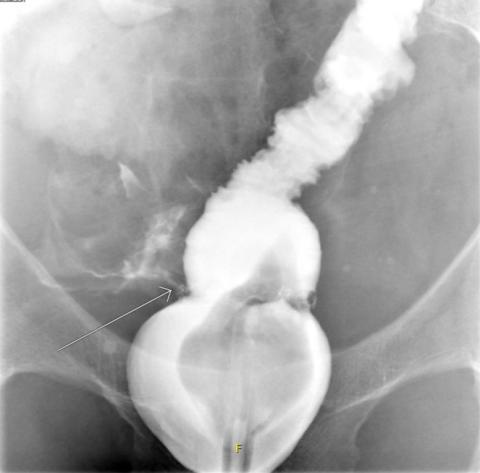

A small leak (arrow) from the colorectal anastomosis following low anterior resection.

The rate of AL was significantly lower in the study group (p < 0.01) than in the control group. There were two cases (4%) of AL in the study group compared with 20 cases (20%) in the control group (Table 4). The two patients in the study group both had small leaks, verified by CT. Both had a diagnostic laparoscopy made where the anastomosis was found to be intact. One of these cases had some degree of peritonitis, and an abdominal drain was established. They both received anastomosis-saving treatment with a transverse colostomy. The colostomy was reversed after one and five months, respectively, following their index operation.